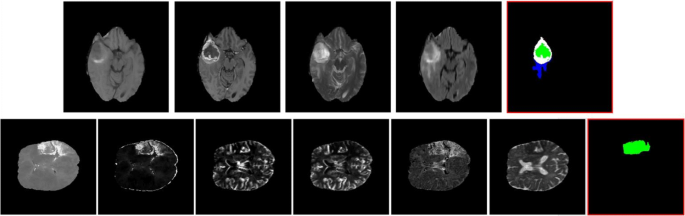

Our goal is to precisely estimate the label of tumor tissues or stroke lesions at each voxel, by using multiple 3D MRI modalities as input, such as {T1, T1-contrast, T2, FLAIR} MRIs for brain tumor segmentation, or {TTP, Tmax, rCBV, rCBF, MTT, ADC} MRIs for stroke outcome prediction, as shown in Fig. 1. For brain tumor segmentation, our model predicts four tumor tissue sub-compartments - necrotic core, oedema, non-enhancing and enhancing core, as defined in [16]. An exemplar image is shown in Fig. 1, where different colors in the predicted results indicate various tumor tissues. Stroke lesion outcome prediction is a binary segmentation task, as shown in Fig. 1, describing expected brain tissue loss post-mechanical thrombectomy on follow-up imaging.

Examples of multi-modality brain MIRs for brain tumor segmentation (from BRATS 2015 database [16]) and stoke lesion segmentation (from ISLES 2017 database [17]). Top (left → right): MRI modalities of {T1, T1-contrast, T2, FLAIR} and brain tumor segmentation results (with a RED bounding box); Bottom (left → right): MRI modalities of {TTP, Tmax, rCBV, rCBF, MTT, ADC} and stoke lesion outcome prediction results